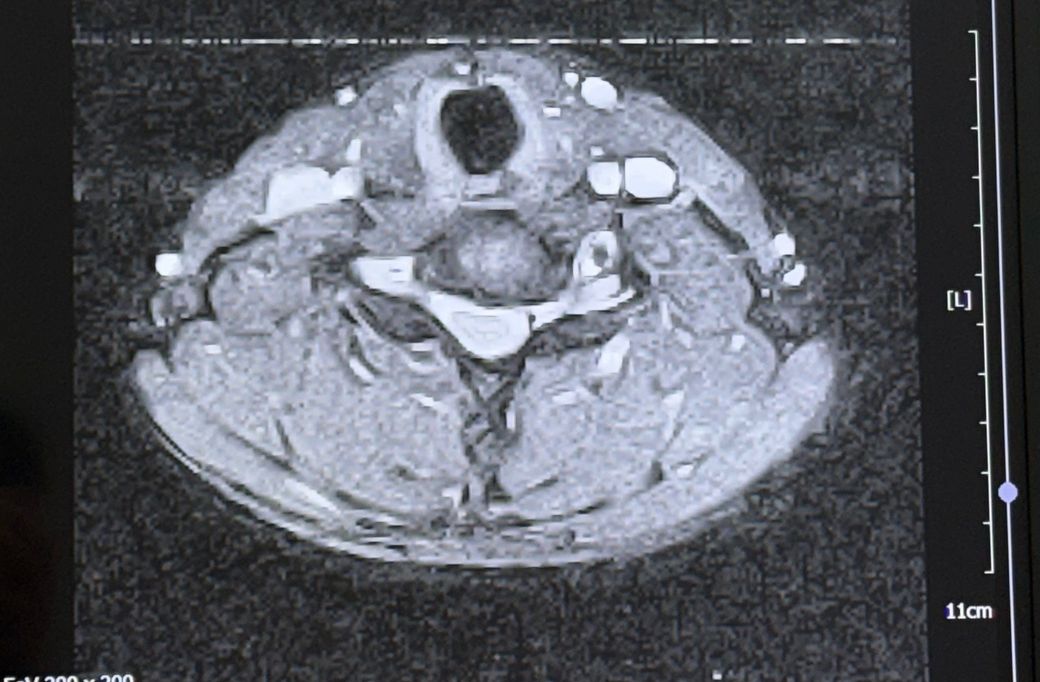

두번째 사진은 경추 6~7번인거같습니다

• 1번 째 사진

• 제공해주신 영상은 경추 MRI로 보이며, 전반적인 정렬은 유지되고 있고 C6–7에서 후방으로 디스크가 돌출된 소견은 확인됩니다. 다만 단일 컷 이미지로는 신경공 협착 정도나 신경근 압박의 정확한 정도를 정량적으로 판단하기는 제한이 있습니다. 척수 자체의 신호 변화는 뚜렷하게 보이지 않아 중증 척수병증 가능성은 낮아 보입니다.

병태생리 측면에서 C6–7 디스크는 C7 신경근을 자극하는 경우가 많고, 말씀하신 검지·중지 감각 이상, 상완 후면 통증, 견갑부 통증은 전형적인 경추 신경근병증 분포와 대체로 일치합니다. 단순한 “목을 젖힘” 동작 하나로도 기존에 약해져 있던 섬유륜이 순간적으로 더 벌어지면서 디스크 팽윤이 악화되어 증상이 유발되는 경우는 실제로 흔합니다.